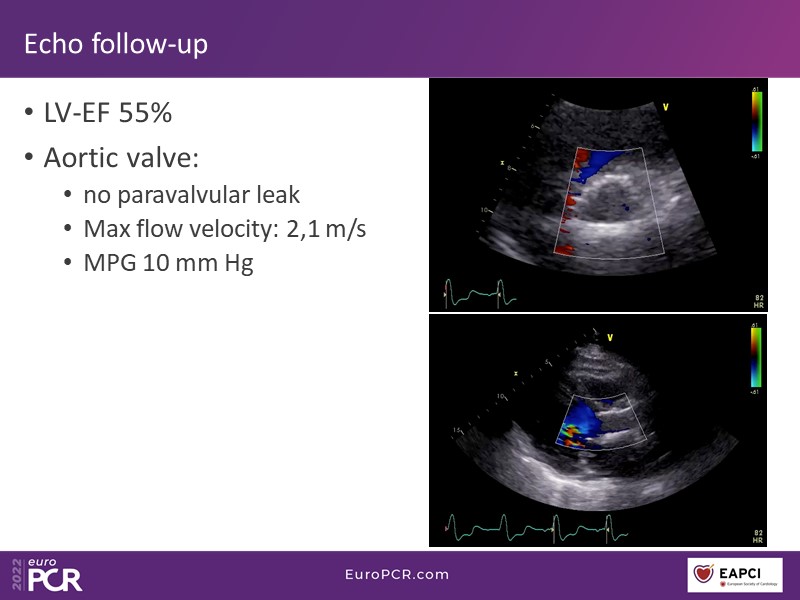

How to deal with challenging anatomies? Find answers in this EuroPCR 2022 session with case studies to explore and learn how to achieve optimal patient outcomes with Evolut platform, uncover practical tips and techniques to achieve implant precision and control, and become familiar with technical considerations and procedural execution of TAVI.